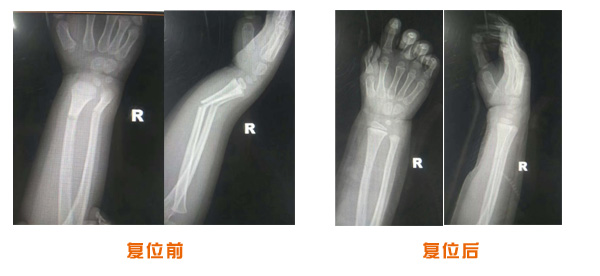

尺橈骨克雷氏骨折治療前后